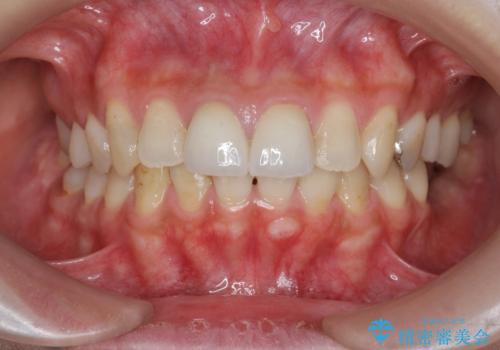

前歯をきれいにしたい

- 「 以前神経を取った歯の変色が気になる。前歯をきれいにして欲しい。」と治療を希望され来院されました。

目立つ上顎前歯に変色・大きな虫歯治療痕が見られ、審美障害を引き起こしています。